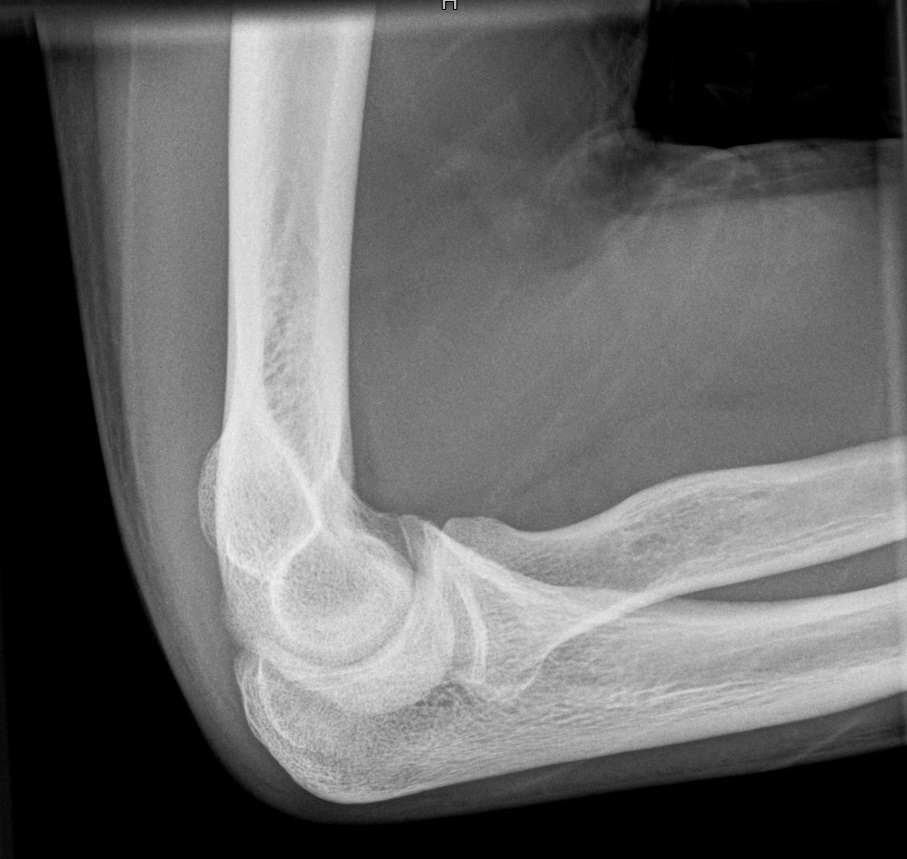

Ellenbogen seitlich

Ellenbogenseit.jpg

Fehler

Der distale Oberarmteil ist schräg projiziert, d.h. die beiden Gelenkrollen überdecken sich nicht, sondern erscheinen über- resp. untereinander. Ursache hier ist die Schrägprojektion bei hängendem Oberarm.

Abhilfe

Es müssen Oberarm und Unterarm auf Schulterhöhe waagerecht aufliegend.